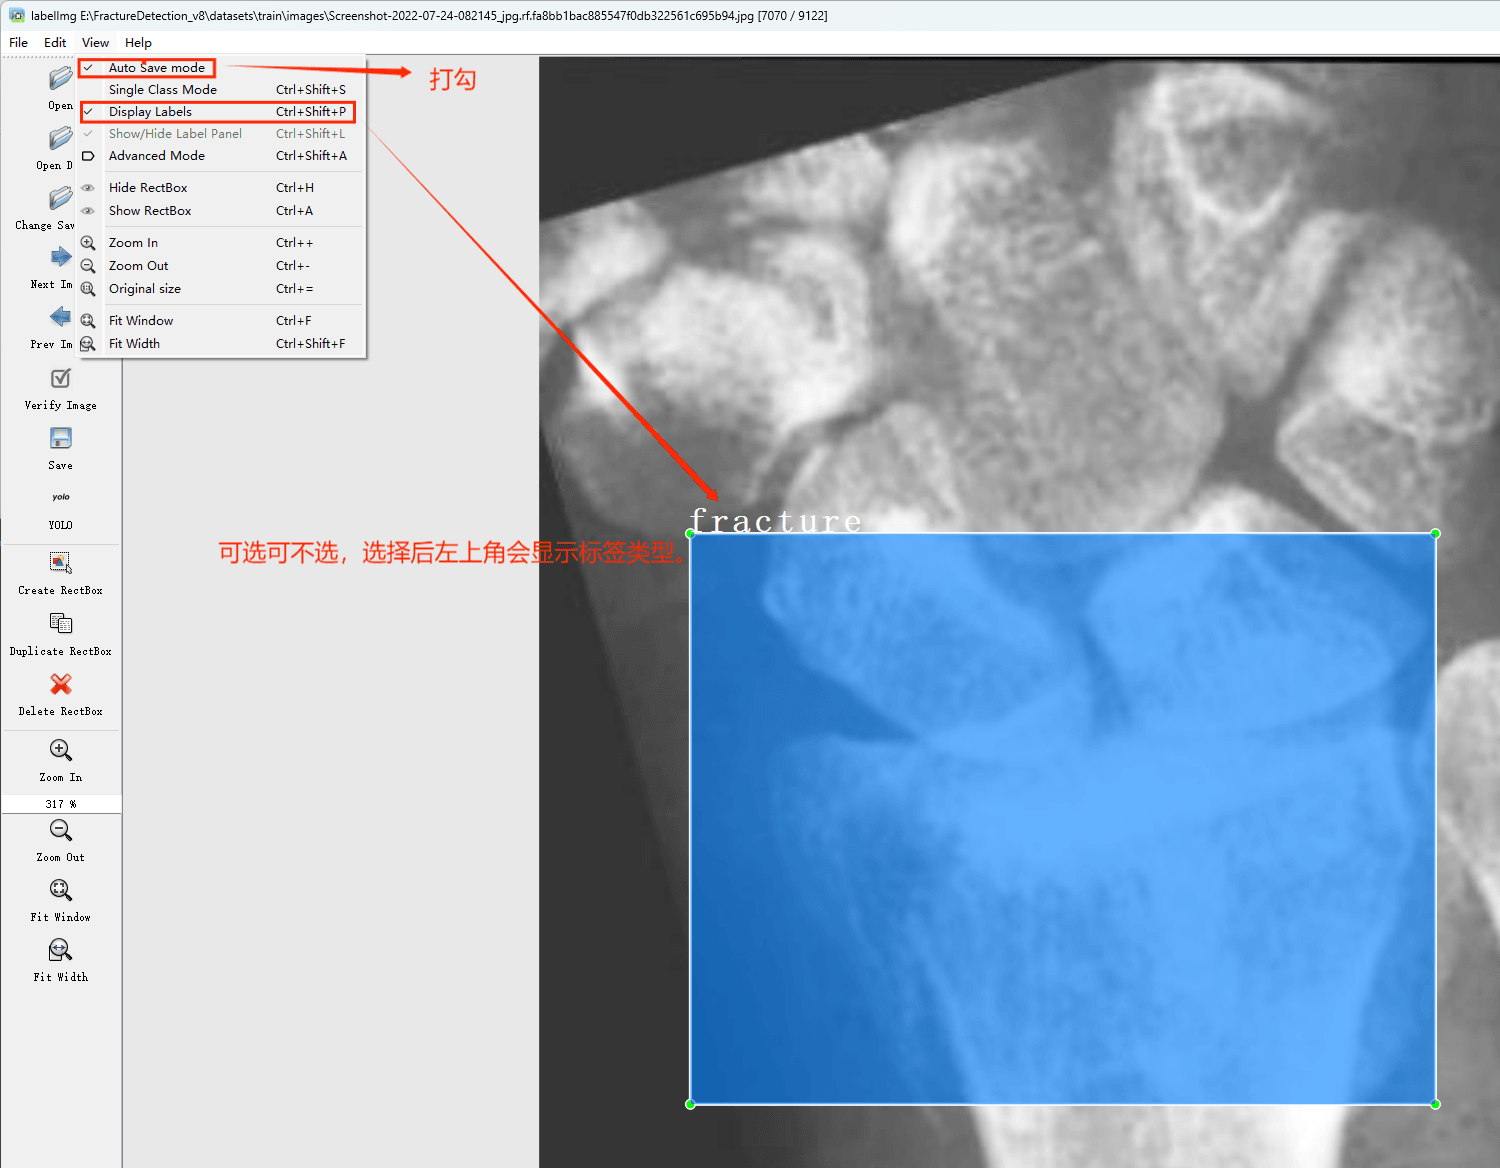

在View中勾选Auto Save mode

接下来我们打开需要标注的图片文件夹

并设置标注文件保存的目录(上图中的Change Save Dir)

接下来就开始标注,画框,标记目标的label,然后d切换到下一张继续标注,不断重复重复。